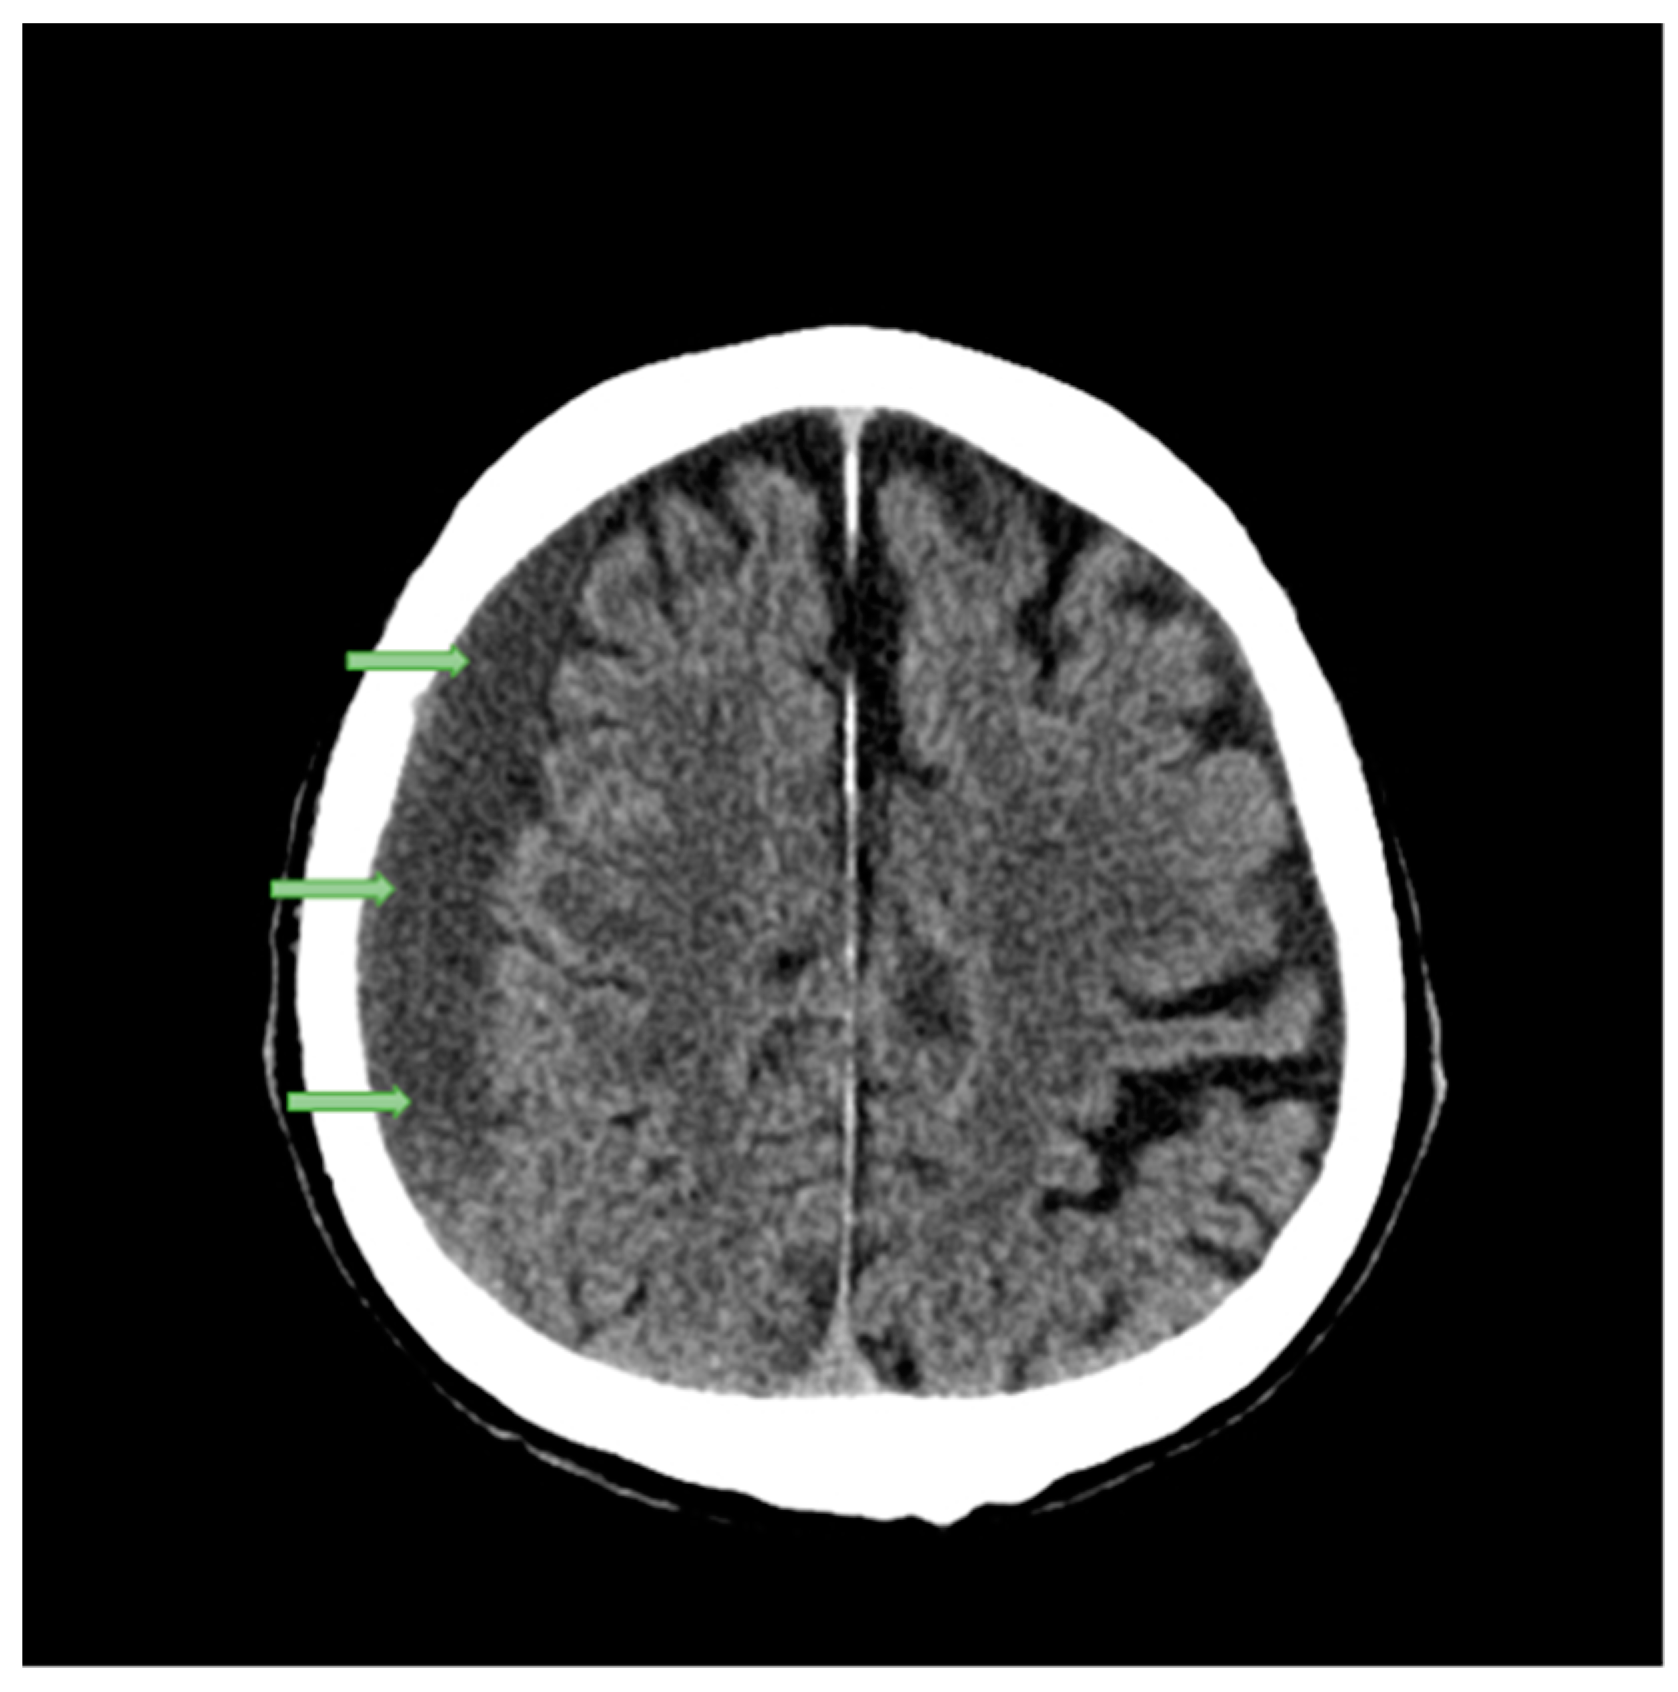

| Brain Parameters (White and Grey Matter) | Young Adults (28 y) ![]() | Senior (77 y)![]() | Difference (Young Adult vs. Senior) | Comments |

| Brain Volume | 1.0406 [dm3] | 0.98088 [dm3] | 5.7% | Young Adults: On average, young adults tend to have larger brain volumes compared to older adults, with a ~6% difference. This is largely due to ongoing brain development and growth during childhood and adolescence [40]. Senior Adults: Brain volume typically decreases with age. This reduction can be attributed to factors such as loss of neurons and their connections, as well as changes in brain structural integrity. This decrease in volume can affect various cognitive functions. |

| Brain Area | 165,893.3 [mm3] | 1,619,62.1 [mm2] | 2.4% | Young Adults: Younger individuals generally have a larger brain area compared to older adults, with a ~2% difference. The brain area encompasses the surface of the brain, which is important for processing information and facilitating communication between different brain regions. Senior Adults: Over time, there may be a slight reduction in the brain’s surface area. This could be related to the gradual decline in cognitive functions, such as memory and processing speed, experienced by some older individuals. |

| Brain Mass | 1.18 [kg] | 1.02 [kg] | 13.3% | Young Adults: Young adults typically have greater brain mass compared to older adults, with a ~13% difference. Brain mass is closely related to brain volume and is largely responsible for the organ’s overall functionality. Senior Adults: As individuals age, there is often a decline in brain mass, primarily due to a decrease in the number of neurons and synaptic connections. This mass reduction can contribute to age-related cognitive decline. |